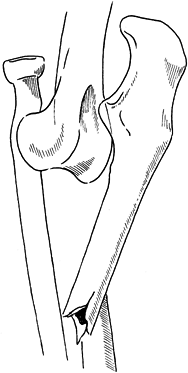

ulna fracture is anatomic restoration and plating (Fig. 16.16).

![]() |

Figure 16.16. Type 2 Monteggia lesion. A: Posterior radial head dislocation in association with a proximal ulna fracture. B,C:

Anatomic restoration of the ulna fracture with plate fixation and interfragmentary compression, and reduction of the radial head. |